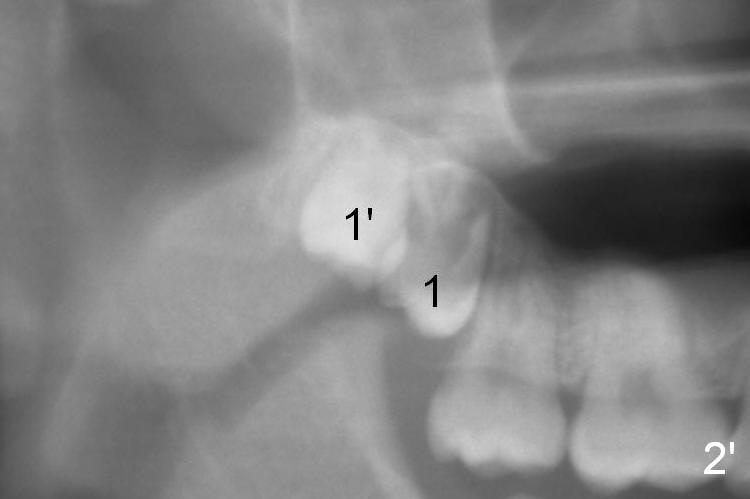

A 18 year old man has fully developing jaws.  It appears that there is enough room for 4 3rd molars to erupt normally.  In fact, the teeth #16,17,32 erupt.  Attached are pan taken 2 and 5 years ago (Fig.2,1, respectively).  I wonder whether we can take out one of the upper right 3rd molars and let the other erupt.  If the latter does not happen, #1 and 32 will be extracted.  The teeth #16 and 17 are not to be extracted.  Due to insurance limitation, the pan is not updated.  Thanks.

Now regarding this case.  No surgeon will take out wisdom teeth in a growing patient, which he is (the teeth anyway), without a current panx. So you are diagnosing from a weak position.  Regardless, you can see he has two #1 teeth--supernumerary.  It is clear the lower molars are mesial angularly impacted, with no hope of full eruption.  The upper wisdom teeth are still positioned high above the CEJ of the second molars, making removal difficult and traumatic.  But this is an old X-ray and we cannot make judgments because we know the roots are longer and the upper teeth have probably migrated more coronally.

The 18 year old is a boy, whereas the 29 year old is a lady.  The former needs extraction; the latter ortho.  I love your wood vision, particularly the relationship between Le Fort I and sleep apnea.  I did think of Le Fort I initially.  I am afraid that it may be the last resort, if there is such a need.  Look at Fig.1',2'.

Panoramic X-ray is taken immediately post extraction of one of the upper right 3rd molars (Fig.3,3') and 20 months postop (Fi.4,4').  In fact the remaining one has erupted normally.